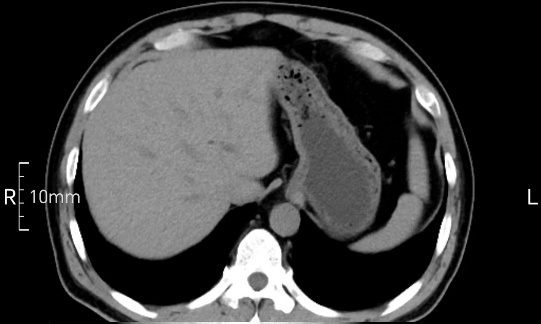

看看下面三幅便知遵醫(yī)囑的重要性。

沒禁食,胃內(nèi)全是食物,導(dǎo)致胃壁顯示不清。